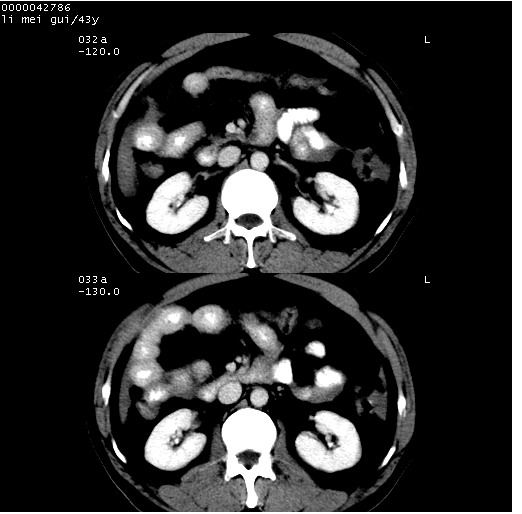

| 患者,男,43岁。突发腹痛2小时,面色苍白,难以平卧。自述近期无明确外伤史,为摩托车驾驶员。 腹部b超检查:脾脏中上极回声异常,肿瘤待排。 临床诊断:腹痛原因待查。 上中腹部ct轴位平扫+增强扫描(层厚10mm,螺距1.0,重建间隔10mm),图像如下: ![]() ![]() ![]() ![]() ![]() ![]() ![]() ![]() ![]() ![]() ![]() ![]() ![]() ![]() ![]() ![]() ![]() ![]() ![]() ![]() ![]() ![]() ![]() ![]() ![]() ![]() ![]() ![]() ![]() ![]() ![]() ![]() ![]() ![]() ![]() zrs发言:支持脾破裂 wwp发言:支持脾破裂并腹水。 xulianj发言:脾脏肿瘤破裂可能性大 zsl6918发言:不像肿瘤出血,考虑还是与外伤后引起的慢性出血有关 zzyy发言:平扫见肝周及脾周积液,脾内密度不均。脾内肿瘤较少见。还是外伤性脾破裂。 沈丘东方医院发言:脾门区一个不均匀强化病灶与其周液体相连多考虑脾占位破裂出血 yixianman001011发言:脾破裂并腹水是可以肯定的,具体原因多以肿瘤性破裂出血,脾脏淋巴瘤可能性大. 结果: 术后,经详细询问患者,其仔细回忆:一月前骑摩托时左侧腰部与别人有“轻微”触碰,因责任在自已,当时又无明显不适,未引起注意。 临床术后诊断:脾破裂并失血性休克(1.外伤性迟发性脾破裂。2.脾脏肿瘤破裂?) 术后标本病检:脾破裂并出血,未见明显肿瘤成份。 原贴地址:http://www.radinet.com.cn/forum_view.asp?forum_id=4&view_id=34070 |